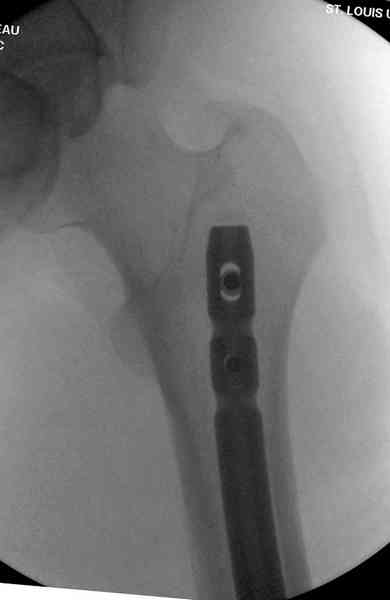

Предыдущей сменой до 4:00 утра по поводу открытого перелома бедра, тибиал плато, пилон и надколенника сделана операция.

Пострадавшему 21 г., травма скоростная, после I&D с расширением раны, на бедре сделана операция ретроградным интрамедуллярным штифтом, остеосинтез с частичной резекцией надколенника и ушивание собственной связки.

На голень наружный фиксатор, рану на бедре ушили (рана была изнутри кнаружи всего 2 см). По протоколу травматических больных, до операции обследован ангиографически, (у больного дистально не смогли определить пульсацию) сосудистый хирург подтвердил проходимость на всем протяжении магистрального сосуда нижней конечности по снимкам ангиограмм.